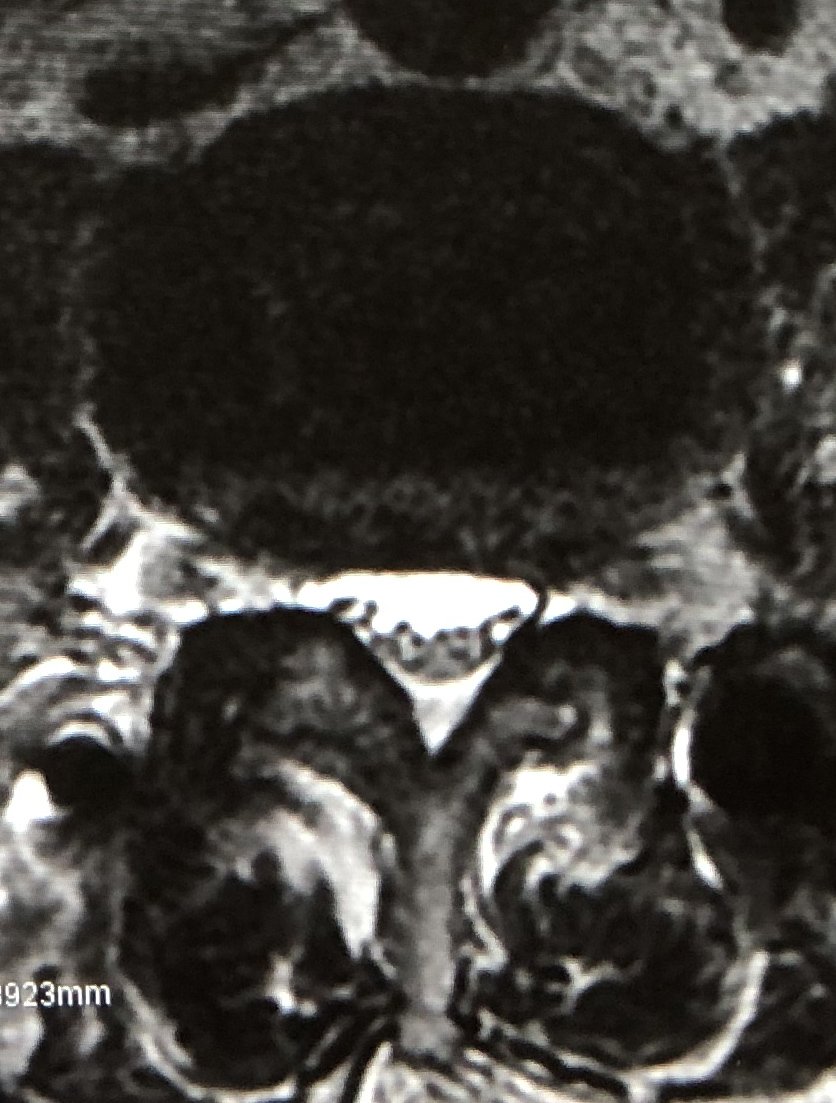

| MRI |

eXtreme Lateral Interbody Fusion(XLIF)は、主に左脇腹からの小皮切で腰椎に側方からアプローチし、脊椎前方に十分な骨移植を行ない脊椎の矯正固定を行なう手術方法です。脊柱管内には一切触れずにす椎間板の高さを増大させてすべりを矯正し、間接的な神経の除圧が可能です。